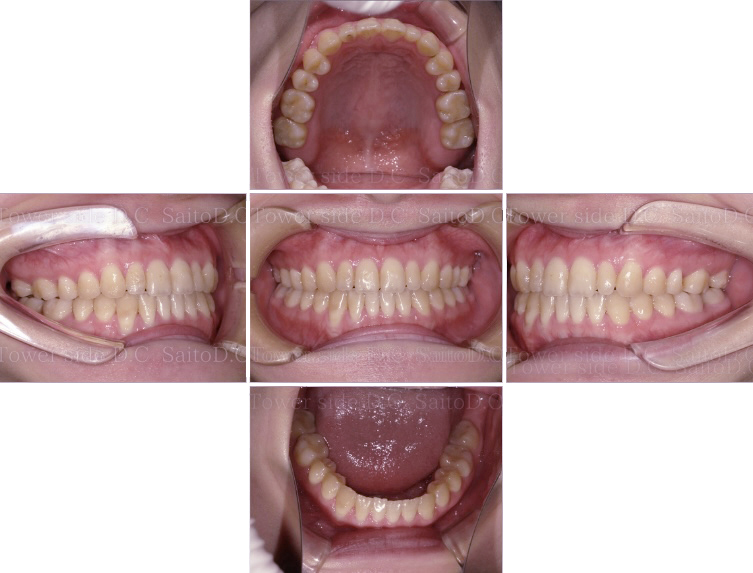

症例(施術前)

症例(施術後)

主訴 上前歯が出ている、上下前歯のガタガタが気になる

状況

• 上顎前歯前突

• 上下顎叢生

• 口唇閉鎖不全有

治療費 880,000円(税込)(自由診療)

治療期間 2年5ヶ月

治療内容 14.24.35.45を抜歯し、ワイヤー矯正にて咬合改善を行った。叢生、臼歯部噛み合わせは改善され、その後保定装置(リテーナー)を使用し安定している。